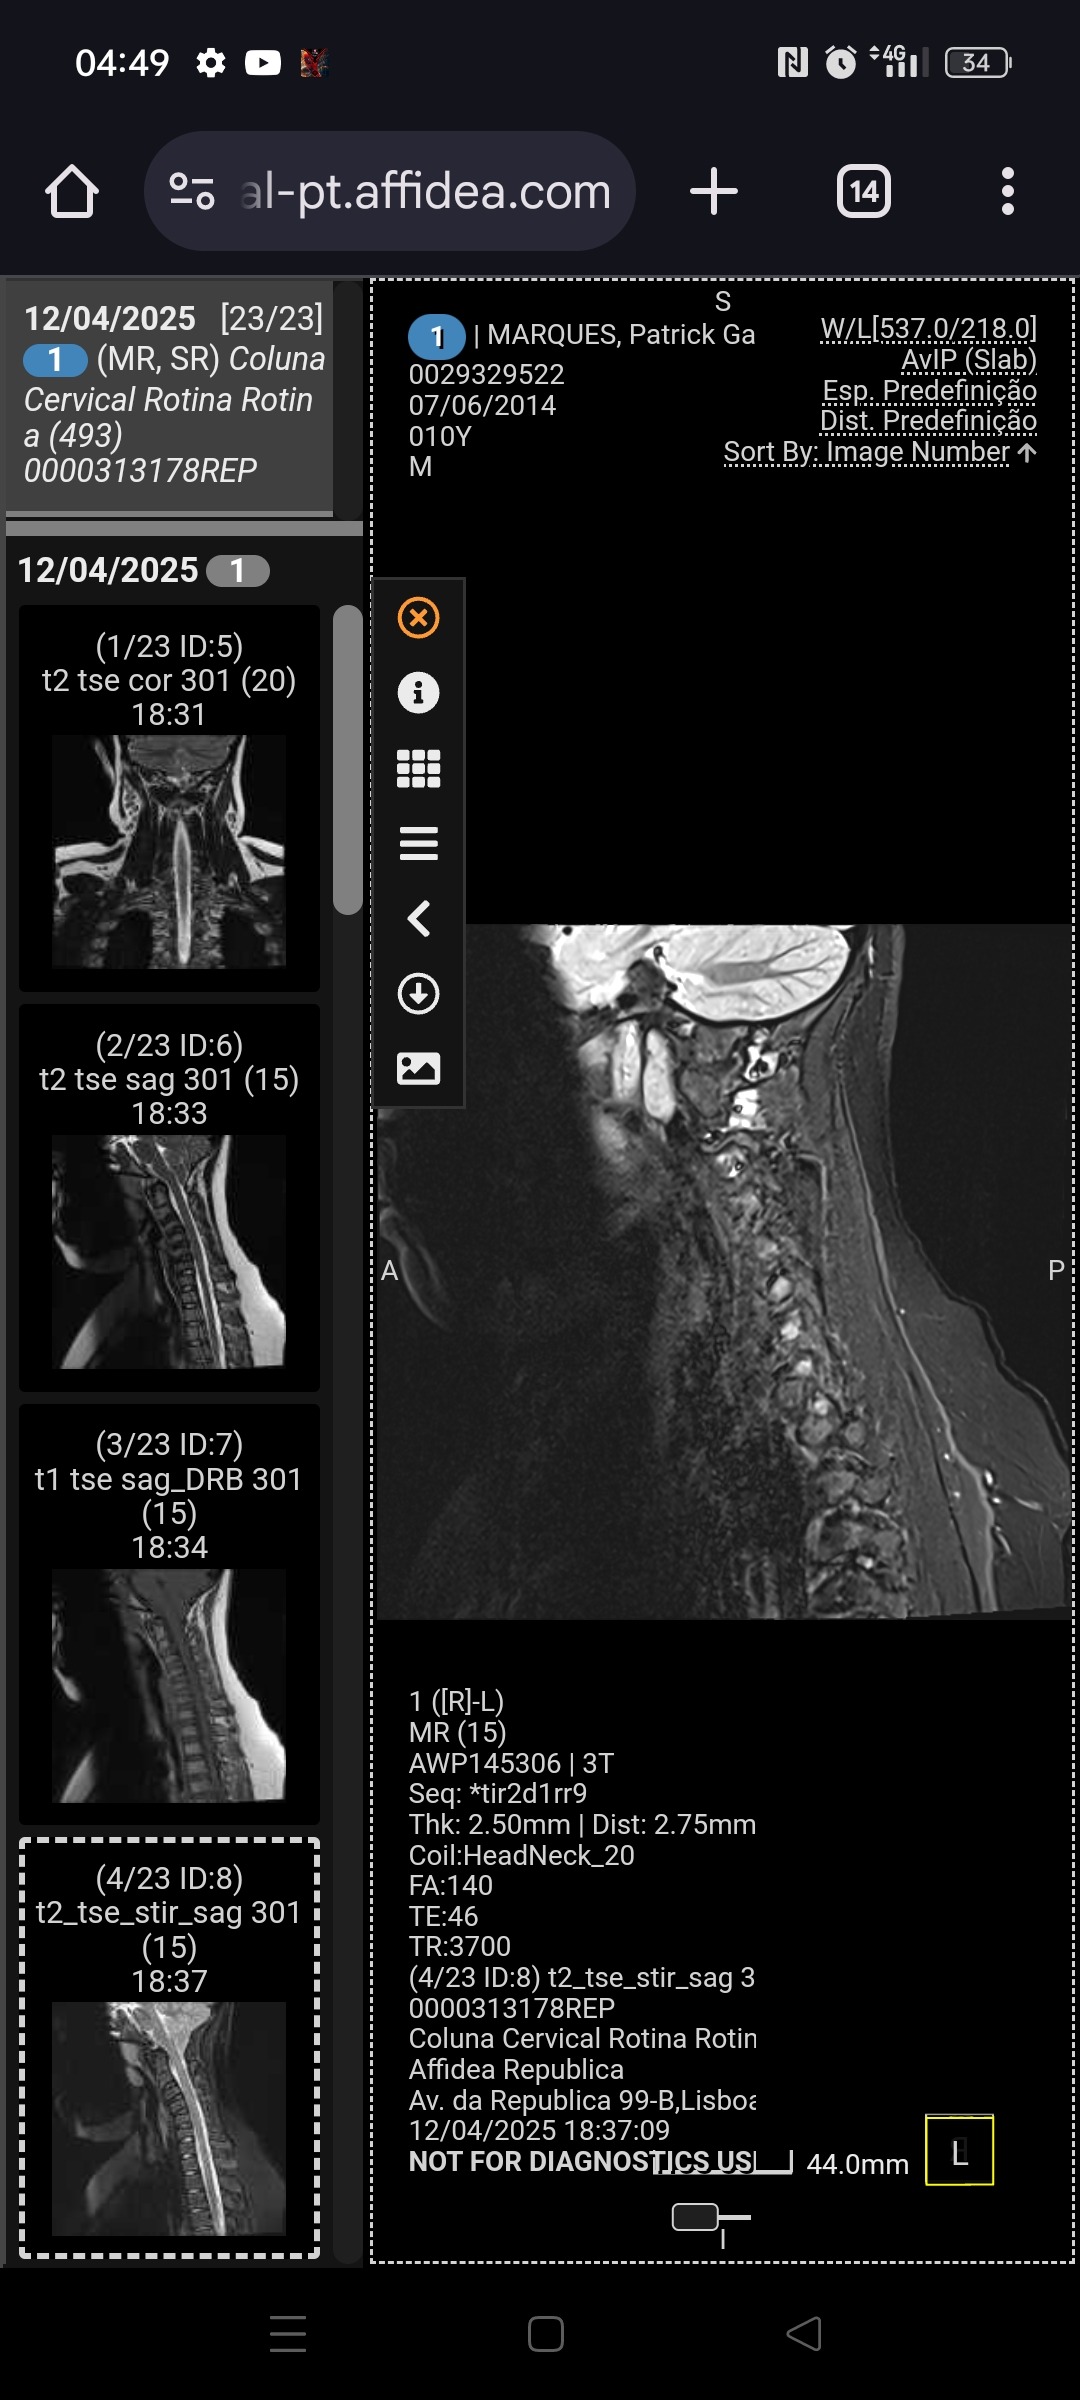

Mas em fevereiro recebemos um diagnóstico difícil: Malformação de Chiari tipo 1, uma condição neurológica que lhe causa dores, tonturas, perda de força e desmaios frequentes.